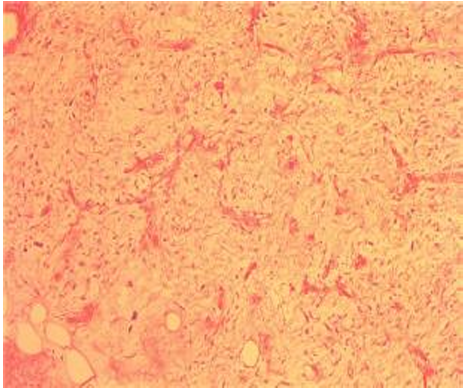

巨检:灰红灰黄质软组织两块,小者大小15.5*15.0*4.2cm,小者切面灰黄质软,大者大小52.3×32.2×8.5cm,大者外有包膜,切面大部分区呈灰白色,局部区域呈灰黄色,局部区域呈胶冻样,局部区域呈灰红色,质地软。予以广泛取材。

病理诊断:(腹腔肿瘤)结合组织学形态及免疫组化,考虑去分化脂肪肉瘤(WHO 3级)。建议进一步分子病理检测。

免疫组化染色结果:H(灰红区):S-100(-)、MDM2(+)、CDK4(+)、SMA(-)、Desmin(部分+)、CD34(+)、 Ki-67(60%+)、P53(部分+)、P16(+);R(胶冻样区):S-100(-)、CD34(+)、SMA(-)、MDM2(+)、P53(部分+)、Ki-67(50%+)、CDK4(+)、P16(+)。

特殊染色结果:R(胶冻样区):AB-PAS(-)。